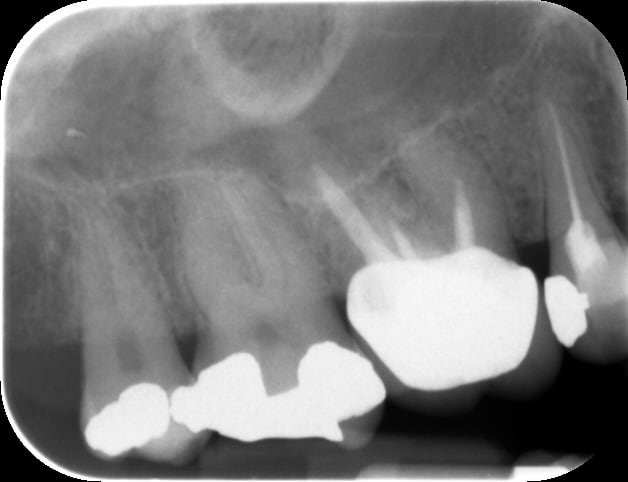

as tu un scan pré op? parfois, la mandibule en coupe a une forte concavité interne, et l'apex de l'implant aurait pu traverser la corticale interne, entrainant oedeme, d'où les symptômes...

+1 scan post op et/ou pré op si tu as, peut être mandibule en baillonnette

pas fait de scan mais j'ai quand même super bien palpé, d'autre part la tuméfaction arrive plus de 10 jours après la pose, si ça avait été ça je pense que l'effet aurait été immédiat, en plus la tuméfaction n'est pas linguale elle est au niveau de l'angle de la mandibule.

Aquarium, je ne vais pas entrer dans le débat scanner obligatoire ou pas, mais si je t'évoque la possibilité d'une concavité importante sous la mandibule, c'est que ton cas me rappelle un cas similaire, ou j'ai du déposer un implant, pour cette raison.

Je travaille régulièrement sans scanner, donc je ne te jette pas la pierre, mais je vais changer de façon de faire, car je suis sur que certains de mes échecs sont dus au manque d'info 3D pré op.